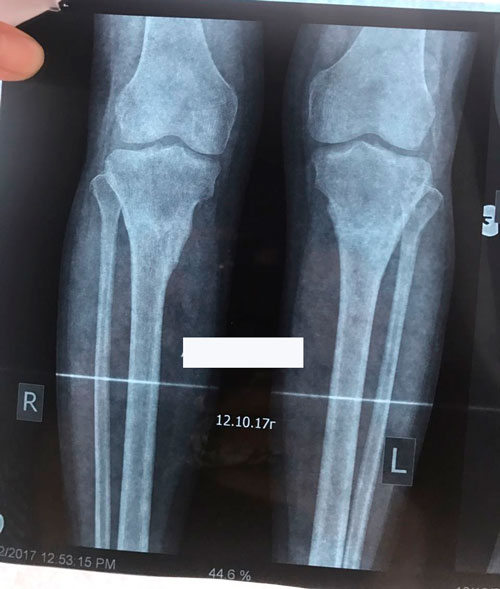

Исходник - 19 лет.

Дата операции 25.05.2017г.

Дата снятия аппаратов 10.08.2017г.

Срок лечения 75 дней.